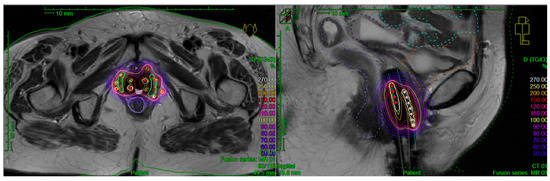

3.3. BT Specification

3.3.1. Implantation Procedure

3.3.2. BT Technique

3.3.3. Treatment Planning Modalities

3.3.4. Target Delineation